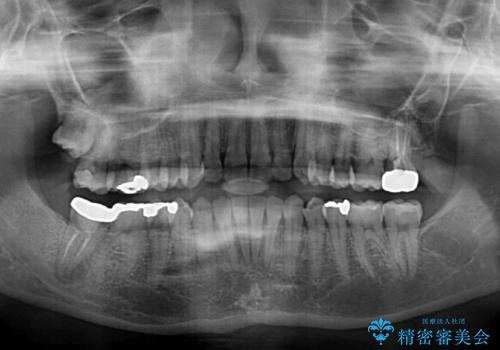

- 上下の前歯のデコボコを治したいとのことで来院された患者様です。

上下顎ともにIPR(歯と歯の間を削る)と歯列全体の拡大によって叢生が解消するように設計し、インビザラインにより治療を行うこととしました。

1日22時間の装着時間を守ってくださったので、比較的早く治療を終える予定でしたが、各国での入国制限が厳しくなり、帰国のタイミングに合わせてのんびりと治療を進めることとなってしまい、やや長期間の治療となりました。